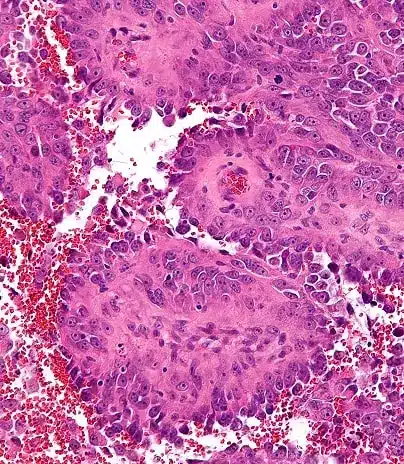

Cáncer de Mama Infiltrante: Una Enfermedad Heterogénea

El cáncer de mama infiltrante, lejos de ser una sola enfermedad, abarca múltiples subtipos con características biológicas y pronósticos distintos. Con los avances en medicina personalizada y farmacogenómica, hoy sabemos que cada tumor es único y requiere un enfoque individualizado.